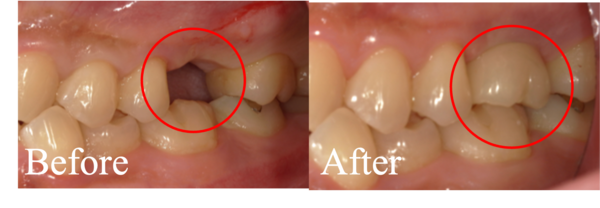

口腔内診察で左上6番目の歯が縦に割れていることがわかり、破折がどこまで続いているかを判断するためにX線を撮りました。こちらが初診時のX線写真になります。

歯の中央部が縦に破折していることがわかりました。

破折は歯髄腔(歯の神経がある部分)にまで及んでおり、当日は痛みを取るために神経を取る処置を行いました。加えて、歯科顕微鏡で歯の内部や破折部を直接確認しました。

破折は3つある歯根のうち1つに限局していました。